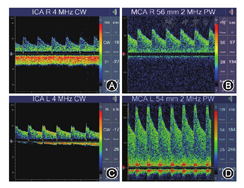

检测方法[2]:用常规方法检测ICA颅外段(4 MHz探头)及颅内Willis环主干血管(2 MHz探头),频谱以最清晰、最大血流速度取样。分析各血管的收缩期峰值流速(Vs)、平均血流速度(Vm)、舒张期末峰值流速(Vd)、频谱形态及音频改变等。一般的,(1)MCA平均血流速度(mean flow velocity of MCA,VmMCA)≥120 cm/s为CVS;(2)计算Lindegaard指数(Lindegaard index,LI),即同侧MCA与ICA颅外段(图4)Vm之比≥3为CVS[8];(3)此外,受检动脉的Vm逐日递增时,要警惕CVS的发生。

A."钉子波";B."振荡波";C、D.微弱的收缩期血流信号甚至无血流信号

2.特殊的频谱提示脑循环停止的可能[1,2]:(1)仅有高尖的收缩期血流、舒张期血流为零即"钉子波"(图6A);(2) 舒张期血流方向逆转,即"振荡波"(图6B);(3)微弱的收缩期血流信号甚至无血流信号(图6C,图6D)。